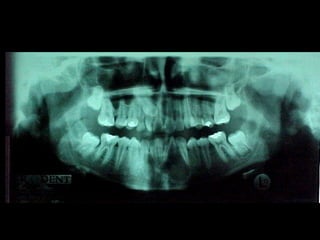

Eliminación de focos sépticos en bloque en paciente con osteitis

mandibular crónica

En el estudio radiográfico determinamos que el factor causal fué un foco séptico

dentario a nivel de segundo molar inferior izquierdo.